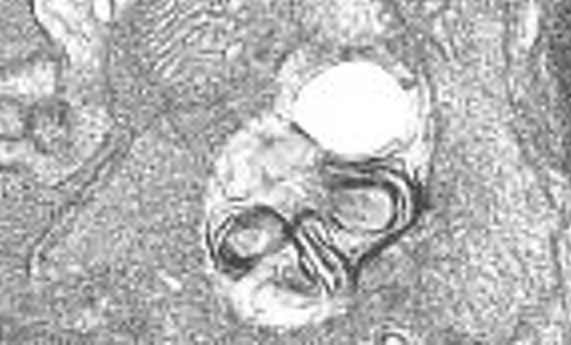

La autofagia resuelve la inflamación retiniana causada por el déficit en IGF-1 en el ratón-

La autofagia resuelve la inflamación retiniana causada por el déficit en IGF-1 en el ratón